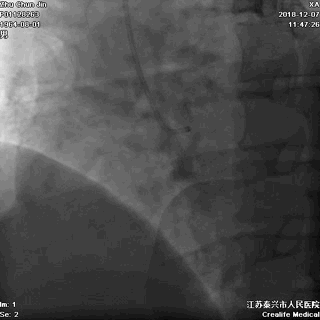

▲左冠无严重狭窄

▲右冠不好找呀!

▲非选择性右冠造影,血管通着咧!

▲在主动脉根部推造影剂,似乎也看不出太多异常

难道胸痛的原因 是冠状动脉痉挛?

胸部透视,看看心影吧:

▲胸部透视见纵隔影似乎明显增宽!是夹层吗?